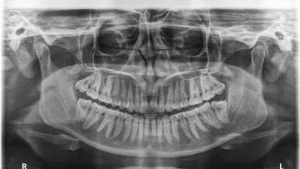

Speech Complaints After Inferior Alveolar Nerve Block: Clinical Reality or Patient Perception?

Main Content Every dentist has heard it at least once after an Inferior alveolar nerve block—“Doctor, I cannot speak properly after the injection.” Patients often